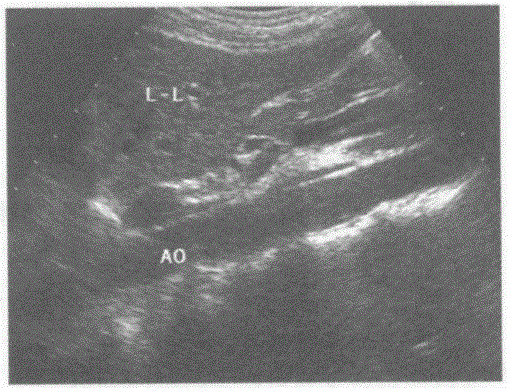

请回答下图是采用哪种肝脏扫查方式:A.肝一下腔静脉纵切声像图B.肝一腹主动脉纵切声像图C.肝一胃纵切声像图D.肝一胆囊纵切声像图

选项 A.肝一下腔静脉纵切声像图 B.肝一腹主动脉纵切声像图 C.肝一胃纵切声像图 D.肝一胆囊纵切声像图

答案 B